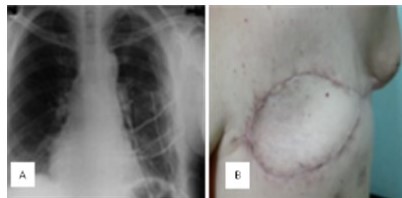

La paciente evolucionó satisfactoriamente, con hemitórax izquierdo hipo-expansible y murmullo vesicular audible en ambos campos pulmonares sin agregados (Figura 8), presenta sin embargo, en herida quirúrgica área de ¨tórax paradójico¨ sin compromiso ventilatorio.

En nuestro caso se utilizaron alambres de Kirschner y malla dual (PROCEED®) con recubrimiento del defecto con colgajo de dorsal ancho que permitió una buena estabilidad de la pared torácica, un adecuado manejo ventilatorio posoperatorio y buenos resultados estéticos (Figura 10). La utilización de la malla PROCEED® por ser dual, es decir, que posee doble superficie, una visceral, lisa que es la que está en contacto con el parénquima pulmonar y otra corrugada, cara parietal. La finalidad del uso de este tipo de malla aparte de brindar una cobertura del defecto creado por la resección, es brindar una superficie que simule la pleura. Esta se fija en los bordes, más no en la zona central, es lo que determina que estos pacientes se comporten con un tórax inestable o paradójico, con complicaciones ventilatorias leves o moderadas.

El defecto amplio de partes blandas posterior a la mastectomía total izquierda tipo Halsted no radical, realizada por necesidad en vista de la extensión y compromiso del tumor, se repara con colgajo miocutáneo del dorsal ancho. Este colgajo es ampliamente descrito en la literatura como un colgajo miocutáneo pediculado, cuya pastilla provee una buena cantidad de músculo y piel para cubrir grandes defectos. Nosotros decidimos implementar esta técnica que posee pocas probabilidades de necrosis tisulares, es relativamente rápida y se consigue un muy buen tejido vascularizado, dando en nuestro caso un buen resultado estético.